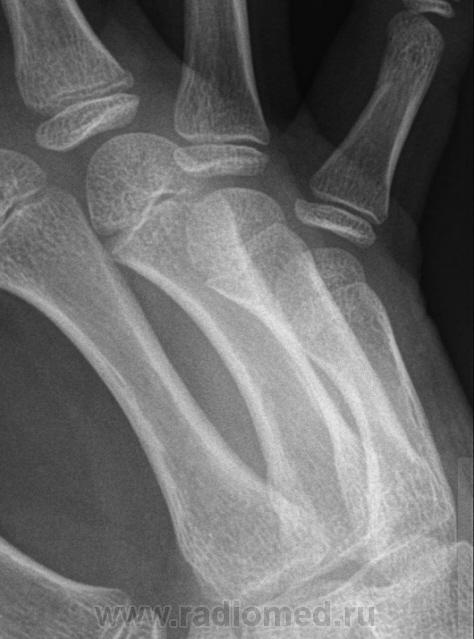

Остеоэпифизеолиз о/ф III пальца.

Интересно, чем можно объяснить такой "грациозный" диафиз 4 пястной кости?

Спасибо Валентин Львович за обработку изображений, в данном случае остеоэпифизиолиз проксимальной фаланги 3п.. В косой проекции кстати даже четко видно ступеньку.

Снимок сделан вчера вечером по дежурству, на Omni-Diagnost(philips).